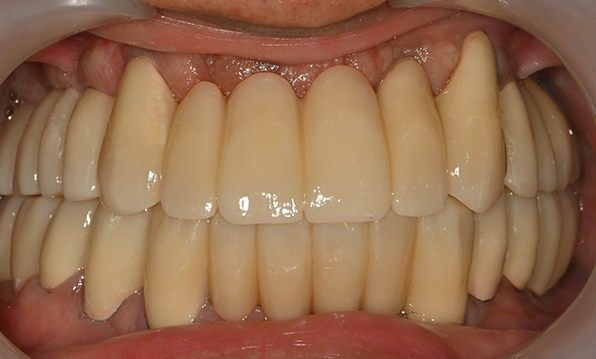

Case 03

Before After